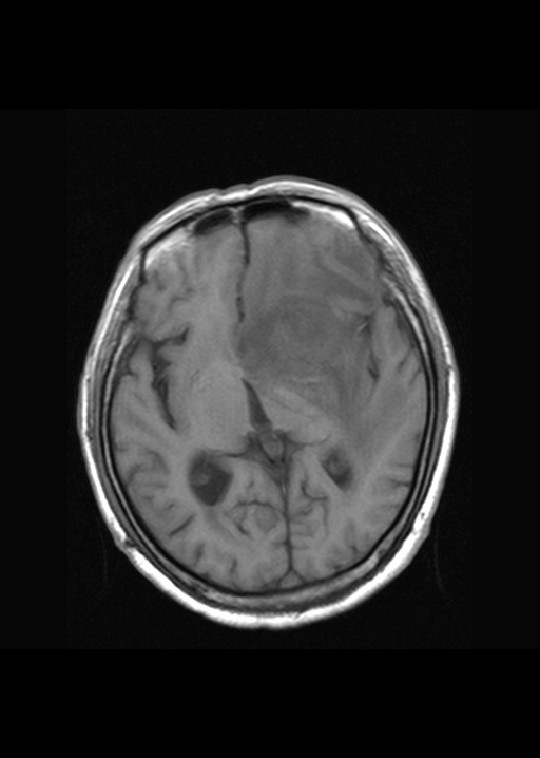

左侧基底节异常信号,水肿带明显,强化明显,考虑胶质瘤

左侧基底节区病灶t1wi呈不均匀稍低信号,t2wi呈稍高信号,周围伴有水肿。增强扫描呈均匀团块样或者抱拳样明显强化,相邻的柔脑膜亦见线样强化。首先考虑淋巴瘤。可惜没有ct平扫,如果ct平扫病灶呈高密度,那么更支持pcnsl的诊断。

左侧基底节区长t1长t2异常团块状信号,增强呈明显均一强化,水肿明显,挤压侧脑室前脚,本人考虑为胶质瘤可能性大。

左侧基底节区病灶t1wi呈不均匀稍低信号,t2wi呈稍高信号,周围伴有水肿。增强扫描呈均匀团块样或者抱拳样明显强化,首先考虑淋巴瘤。